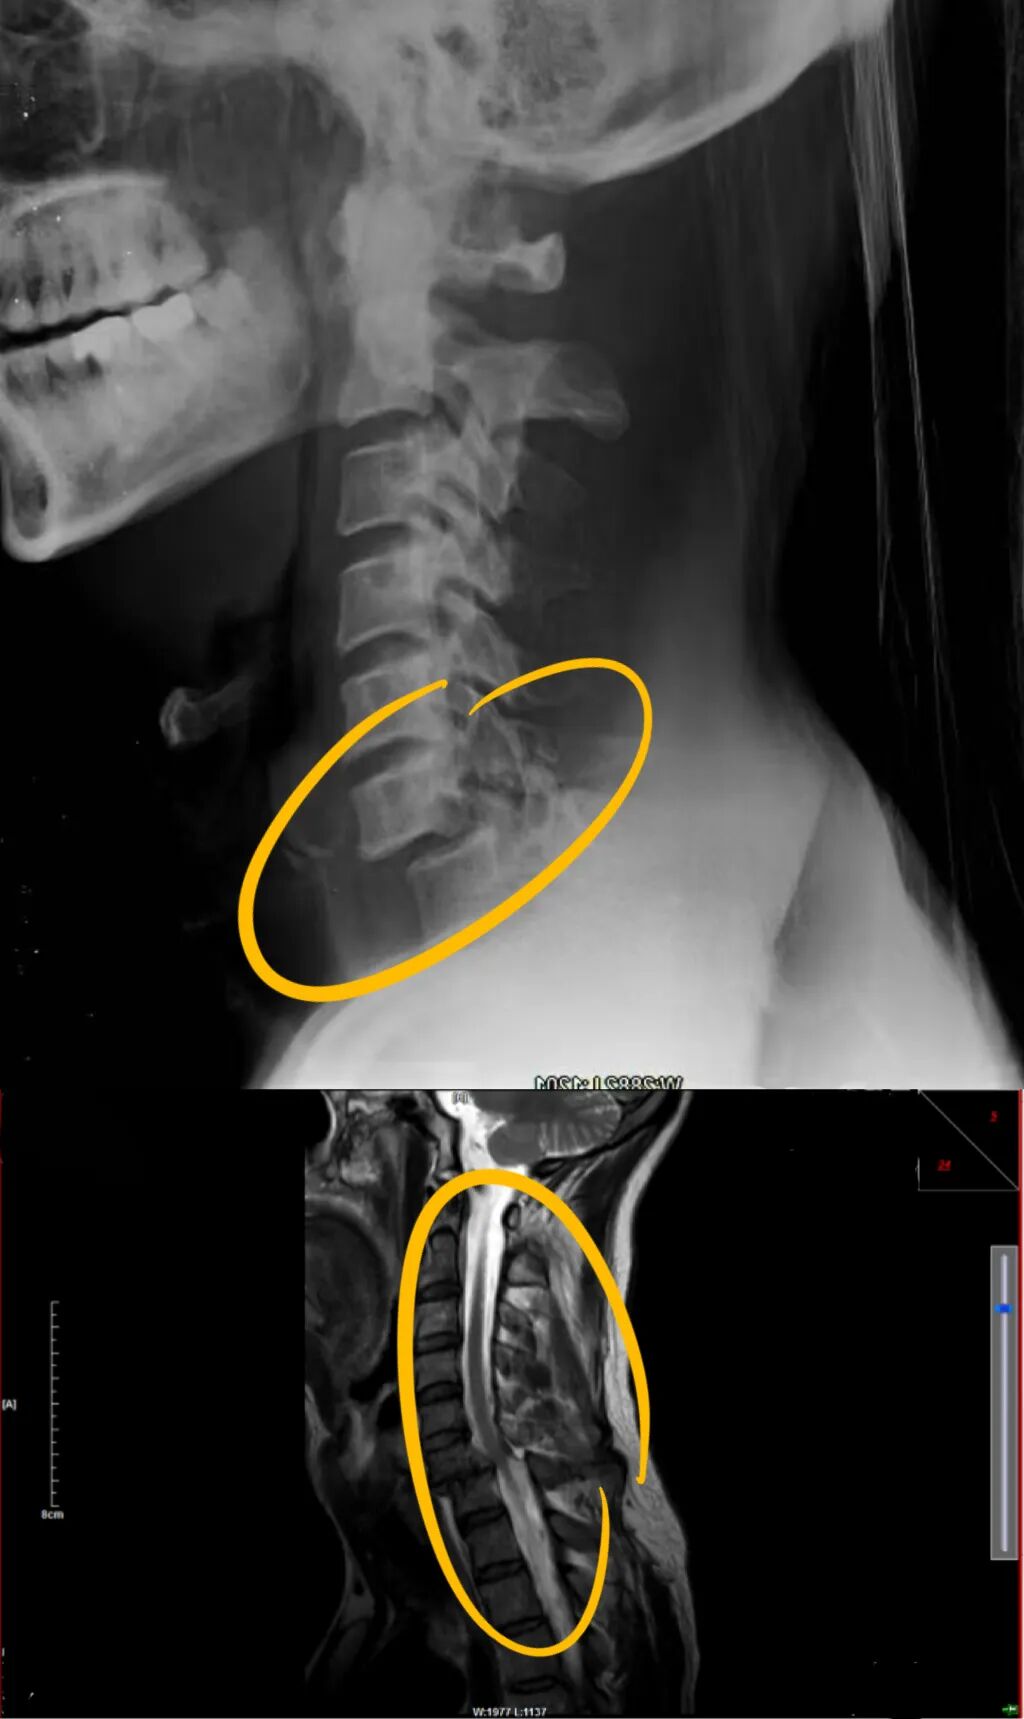

到院后,经过王万垠主任仔细查体及综合影像学检查结果,诊断为:1、颈6骨折脱位并小关节交锁;2、颈髓损伤(ASIA分级C级);3、左胸多发性肋骨骨折并气胸 、肺挫伤;4、左锁骨骨折。“我们先是采取了颅骨牵引,尝试颈椎复位,但患者骨折的位置很特殊,于是又调整了治疗方式。”王万垠主任介绍道。 (术前) 治疗上,王万垠主任组织多学科会诊讨论,并与其家人仔细沟通后,颈部的骨折决定采用“颈后路小关节脱位复位、后路侧块钉棒固定融合术”“颈前路颈6/7椎间盘切除植骨融合内固定术”,术后继续中医药、针灸、理疗康复;“左胸多发性肋骨骨折并气胸 、肺挫伤、左锁骨骨折”由骨三科(正骨科)主任、主任医师李国帅运用“何天佐传统中医药正骨疗法”进行手法复位。经过两周的住院治疗及康复,赵大爷顺利出院。 (术后) “当时听到要手术,我们都非常的担心和焦虑,毕竟他年纪大了,但王主任和周落亮、陈杨帆医生耐心的和我们沟通,也给我们看了很多相似的案例,这才消除了我们的顾虑。”赵大爷家人回忆道。 如今,3个月过去了,赵大爷再次来院复查,经过王万垠主任的仔细查体,发现赵大爷颈、胸、肩痛消失,颈椎及四肢活动度非常好。“真是太感谢王主任了,真是没想到啊,这么短的时间,我能恢复的这么好。”赵大爷激动的说道。